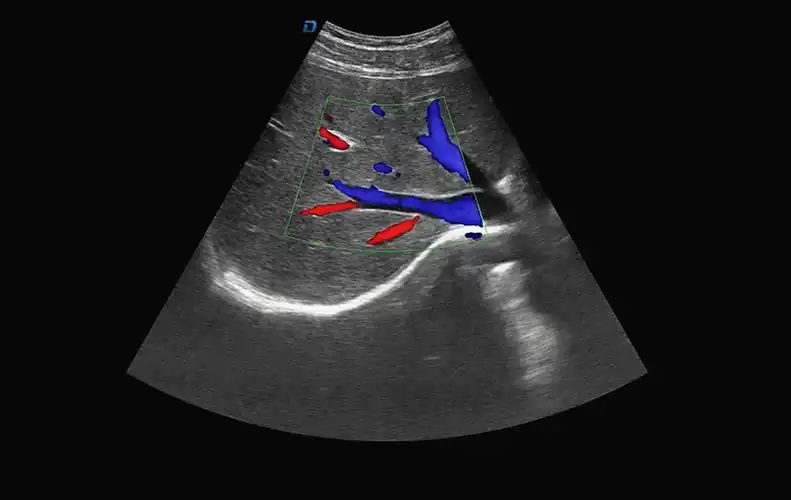

b超机肝脏血流图

二,肝脏超声的扫查方法及正常肝脏的超声图:一,正常肝脏解剖:肝叶和肝

彩超显示肝切面形态大小正常包膜规整肝内回声分布均匀